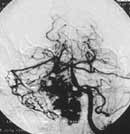

Рисунок. Тот же пациент. (б) Левая боковая проекция.